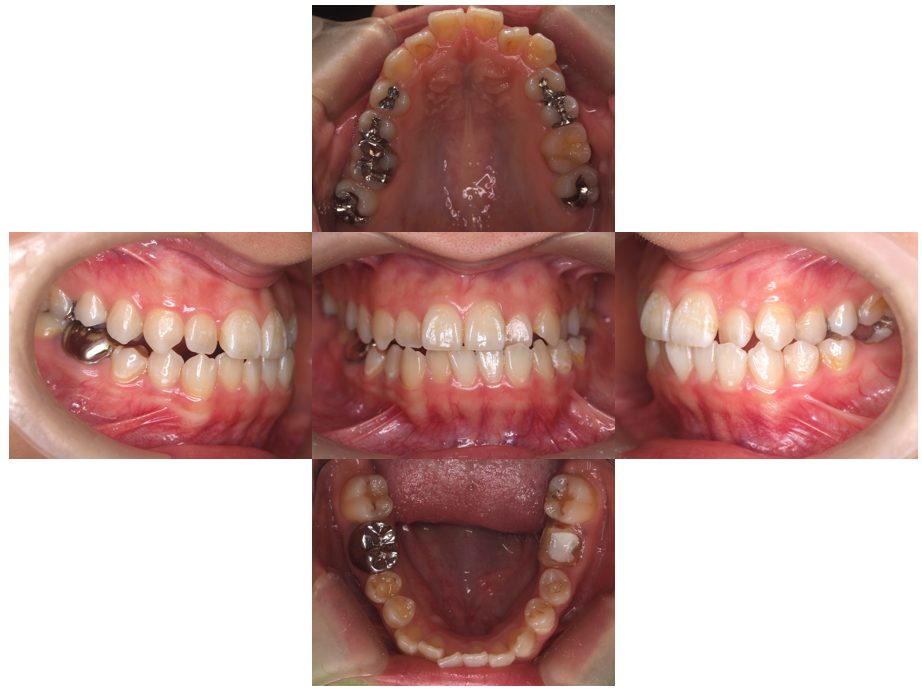

外科矯正治療・インプラント治療の症例紹介(三隅歯科クリニック)

三隅 賢祐(三隅歯科クリニック)

症例詳細

| 主訴 | 20代女性 矯正治療希望。治療途中の歯もあるので治したい。左顎関節が痛い。 |

| 治療内容 | 矯正治療を行いました。 |

| 治療費 | 1,400,000円(税込み) |

| 治療期間 | 3年(矯正治療期間 2年半) |

| 治療回数 | 40回 |

| 想定されたリスク | 顎骨の変形があったので、全身麻酔下による外科処置が必要になり、身体的、精神的負担が増す可能性がありました。 清掃状況によっては矯正中にむし歯が発生するリスクがありました。 |